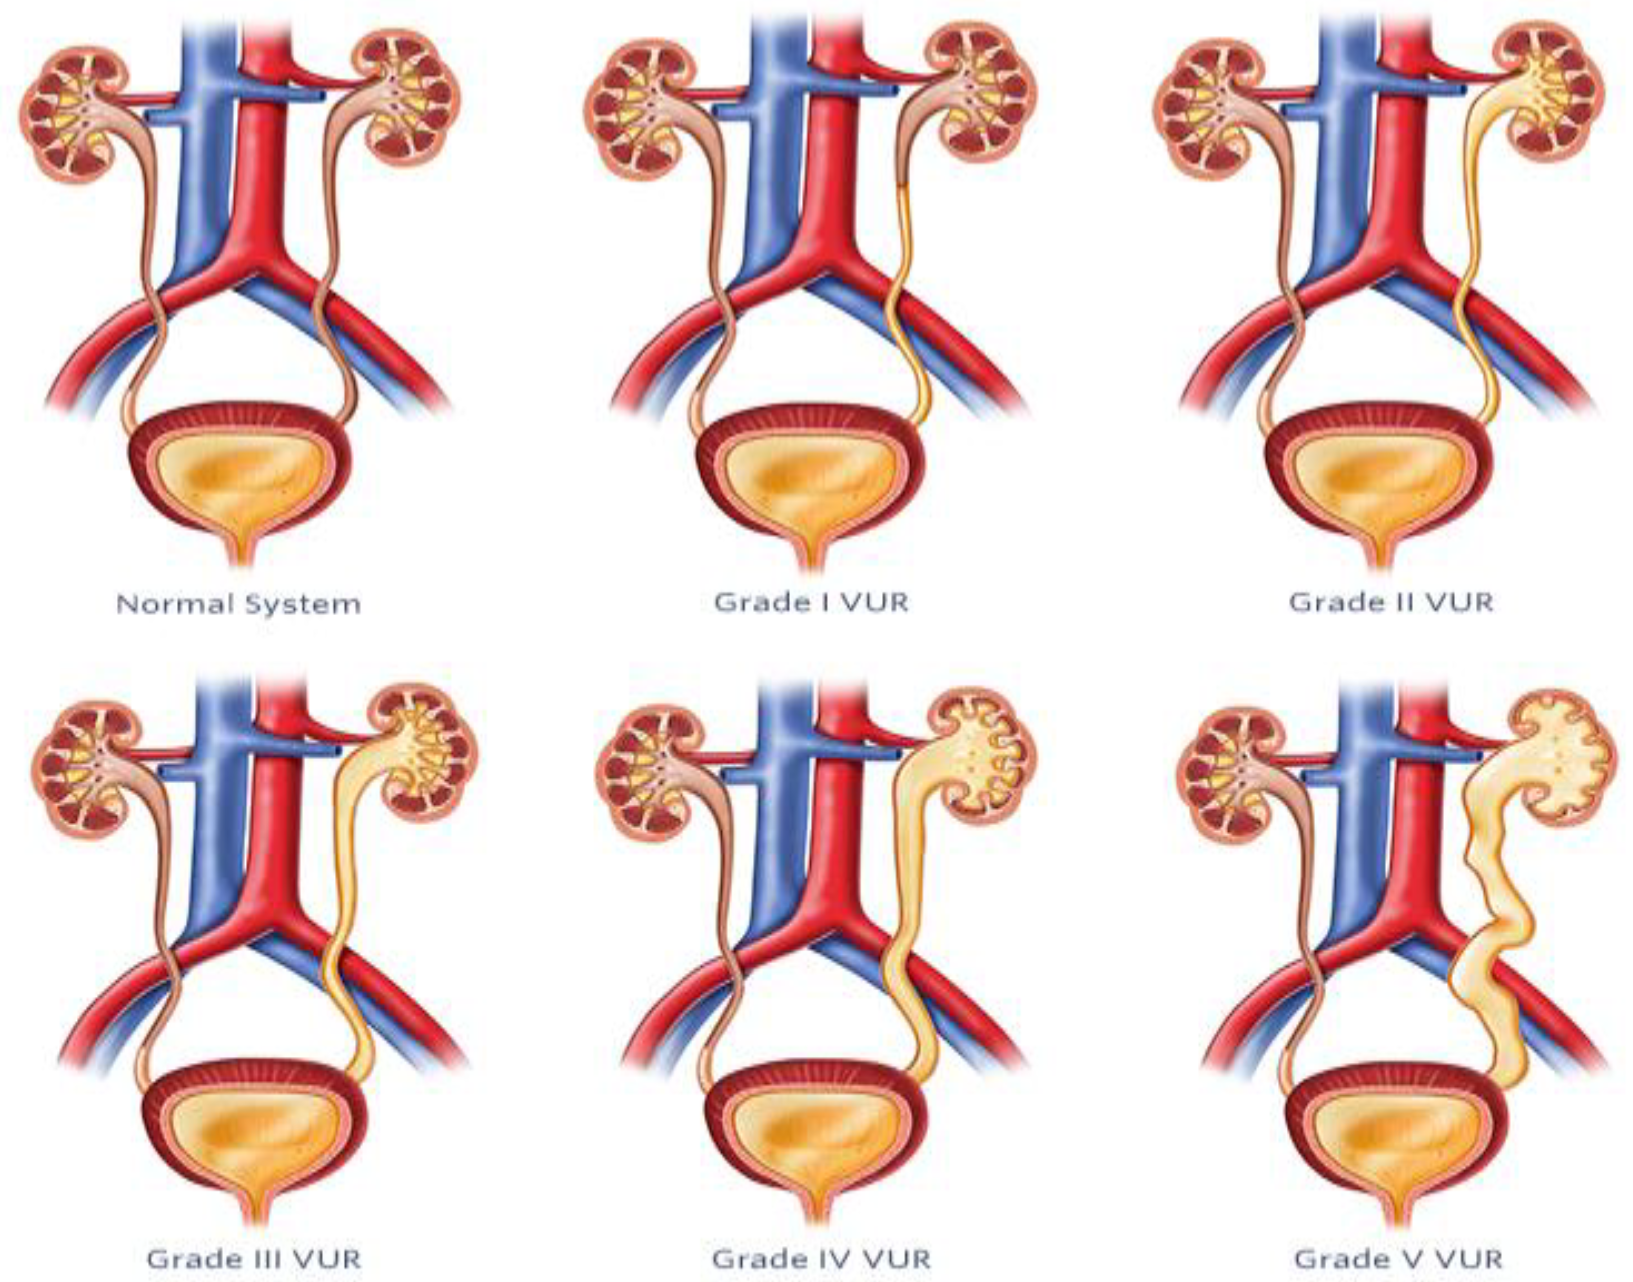

5. Vesicoureteral Reflux

5.1. Diagnosis and Management of VUR

5.2. AI-Based Imaging Techniques

| Machine learning models for VUR [48] | Utilizes ML to automate VUR severity assessment from VCUG images, aiming to reduce subjectivity and improve reliability of evaluation. | Decreases influence of subjectivity, offers uniform diagnostic procedures. |

| Quantitative vesicoureteral reflux (qVUR) [49] | Employs supervised ML to analyze VCUG images for VUR severity, achieving high accuracy and clarity in grading. | Provides a web program for automated grading, ensures impartial and consistent assessment. |

| Contrast-enhanced voiding ultrasonography (ceVUS) [52] | Uses second-generation ultrasound contrast agents and AI algorithms to diagnose VUR, offering a radiation-free alternative to traditional methods. | Enhances ultrasound imaging, reduces risks associated with ionizing radiation. |

| Vesicoureteral reflux index (VURx) [54] | Predictive tool developed for assessing improvement and resolution rates of VUR in children under two years, aiding in tailored treatment plans. | Accurately predicts reflux improvement and resolution, guides clinical decision making. |

5.3. Prediction Models and Long-Term Follow-Up